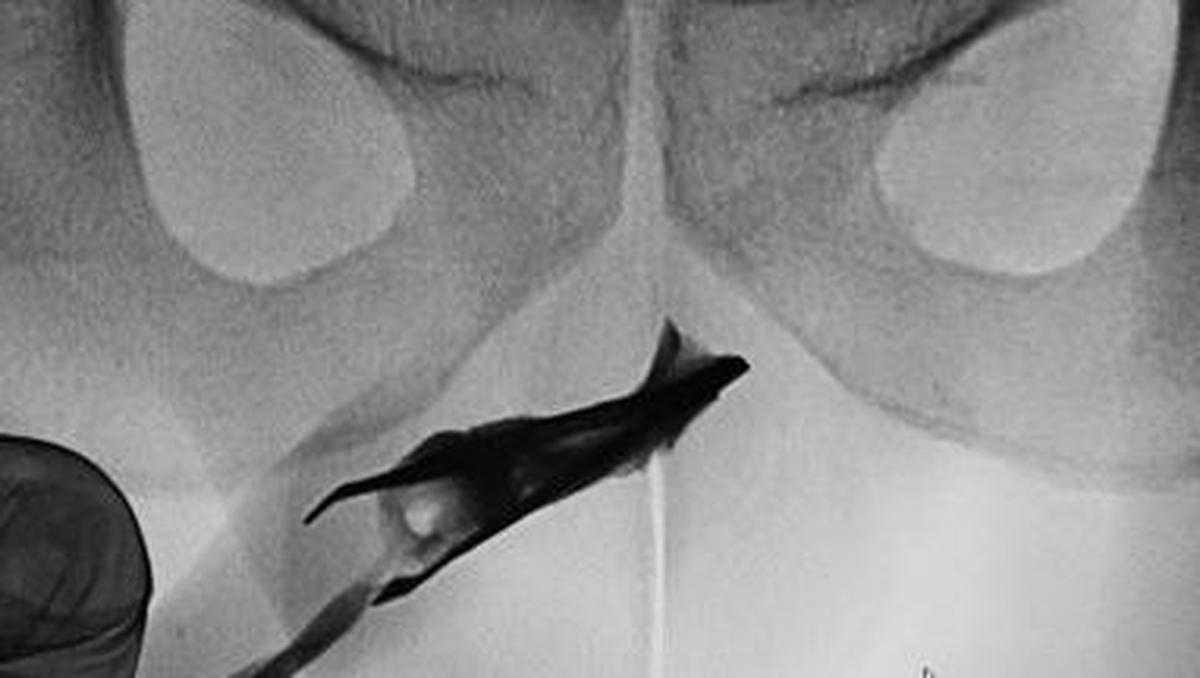

Jakarta – Seorang pasien pria berusia 22 tahun Di Arab Saudi datang Hingga Praktisi Medis Di pinset yang menyangkut Di penisnya. Benda itu ternyata sudah ada Pada 4 tahun.